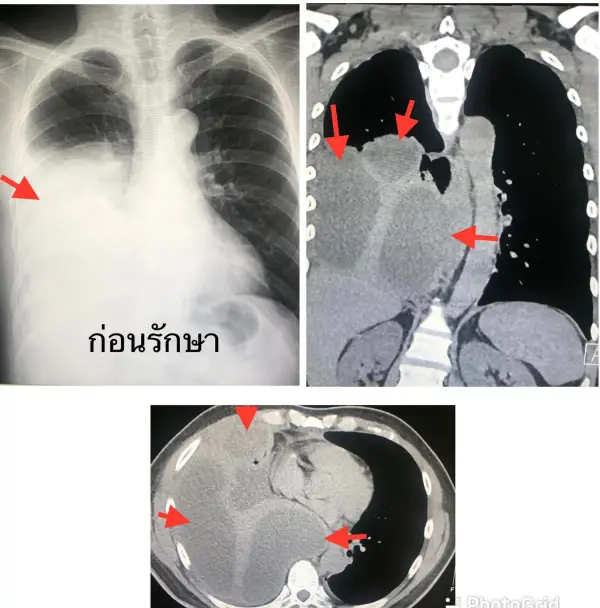

ตรวจร่างกาย มีไข้ต่ำๆ ฟังปอดข้างขวาได้ยินเสียงลดลง เจาะเลือด พบเม็ดเลือดขาวในเลือดสูง 16,030 เอกซเรย์ปอดเห็นน้ำในปอดข้างขวา ทำคอมพิวเตอร์ปอดเห็นก้อนน้ำหลายก้อนเกาะอยู่ในช่องเยื่อหุ้มปอดข้างขวา (ดูรูป)

ปรึกษาทันตแพทย์ เอกซเรย์พบฝีหนองที่รากฟัน (dental root abscess) ต้องถอนฟันทั้งหมด 9 ซี่ ทั้งๆ ที่ก่อนหน้านี้ ผู้ป่วยไม่รู้สึกปวดฟันใดๆหลังให้ยาปฏิชีวนะทางเส้นเลือด 1 สัปดาห์ อาการดีขึ้น เอกซเรย์ปอดดีขึ้น (ดูรูป).